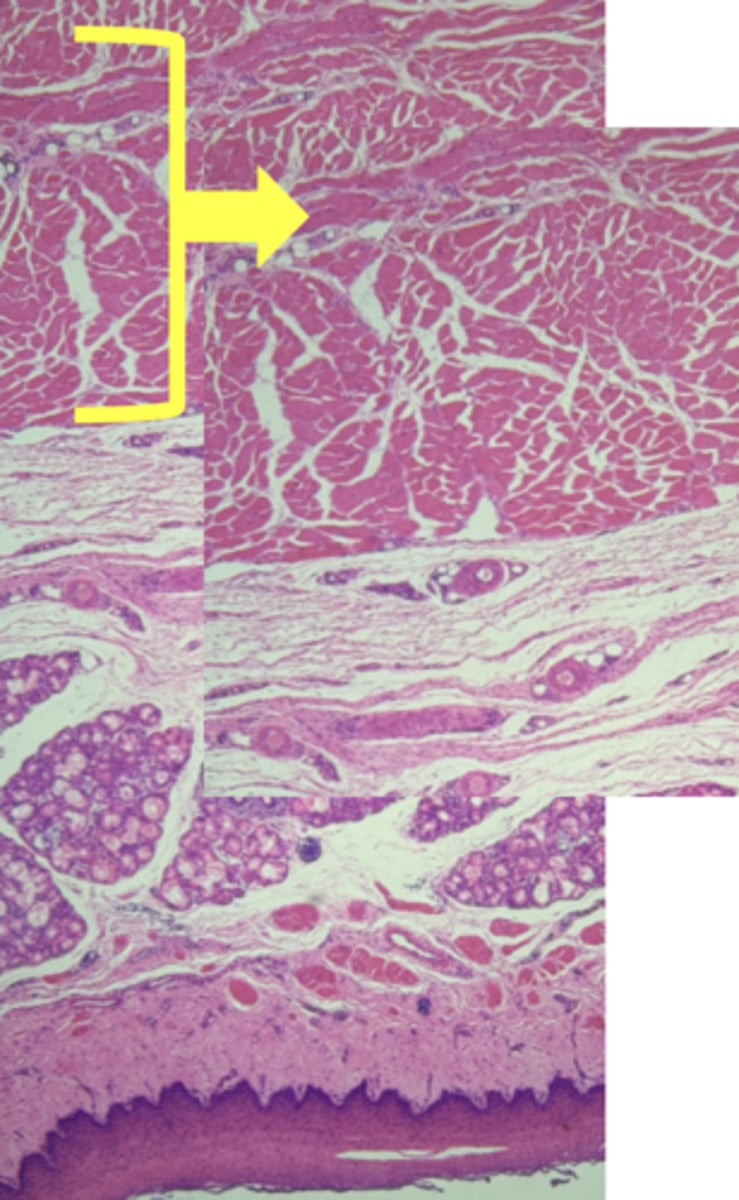

A- Esophagus

B- Stomach

Name the Tissue A & B

stomach

name the tissue

mucosa

(stomach)

submucosa

muscularis externa (3 LAYERS-KEY CHARACTERISTIC)

oblique layer

circular layer

longitudinal layer

simple columnar epithelium

gastric pits (KEY CHARACTERISTIC)

gastric glands (KEY CHARACTERISTIC)

Parietal cells- HCl (hydrochloric acid)

name the cell & what it secretes

Chief Cells- pepsinogen/pepsin

Lamina propria

muscularis mucosae